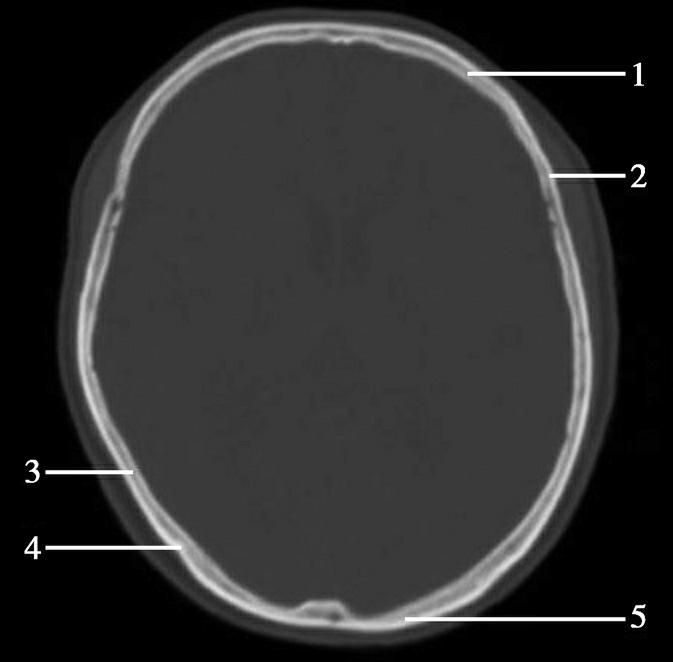

重要结构:中央沟、额叶、顶叶、中央旁小叶、中央前回、中央后回(图1-2-46~图1-2-48)。

图1-2-46 中央旁小叶下部层面

A.横断面;B.横断面标注

1.上矢状窦;2.大脑镰;3.额叶;4.中央前沟;5.中央前回;6.中央沟;7.中央后回;8.中央后沟;9.中央旁小叶;10.缘上回;11.角回;12.顶上小叶;13.楔前叶

图1-2-47 中央旁小叶下部层面(骨窗)

1.额骨;2.冠状缝;3.顶骨;4.人字缝;5.枕骨

图1-2-48 脑叶划分示意图

F.额叶;P.顶叶

此层面通过扣带沟上方的中央旁小叶,位于大脑镰两侧中部偏后,其前方为额内侧回,后方为楔前叶及楔叶,外侧为两半球的放射冠,放射冠的外侧可见中央沟及中央前、后回,中央沟仍位于大脑凸面中部,常为大脑半球外侧面三条较深脑沟中的中间一条。中央前回的前方为额上回、额中回。断面后部内侧为楔前叶及顶上小叶,此叶外侧为角回,角回前外侧为缘上回。此层面已无枕叶。大脑镰位居中线,其前、后端可见上矢状窦断面。